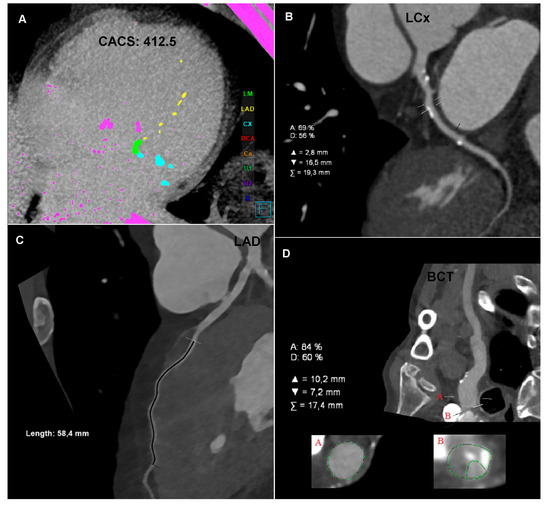

The CTA of the coronary arteries, performed using a 384-slice Siemens Force CT, revealed a coronary artery calcium score of 412.5 (left main (LM): 185, left anterior descending (LAD): 16.7, and left circumflex (LCx): 210.8), the value of which indicated a high risk of a significant coronary artery disease (Figure 1A); the examination revealed numerous atherosclerotic plaques of various morphotic types in the coronary arteries, causing short-segment stenosis, up to 50–70% within the left circumflex, right behind the origin of the 1. marginal branch (Figure 1B) and the long muscular bridge within the middle section of the left anterior descending, about 5.8 cm long (Figure 1C). The CTA images of the coronary arteries corresponded to level three in the CAD-RADS classification, meaning a moderate coronary disease with the presence of moderate LCx stenosis requiring an objective evaluation, optimally via functional tests [1].

Figure 1.

Computed tomography angiography (CTA): (A) Coronary CTA. Native phase. Axial reconstruction. Coronary artery calcium score measurement. The colors indicate the calcifications assigned to specific coronary arteries. (B) Coronary CTA. Angiographic phase. Curved multiplanar reconstruction (cMPR). Left circumflex (LCx). Measurement of the degree of stenosis. (C) Coronary CTA. Angiographic phase. Curved multiplanar reconstruction (cMPR). Left anterior descending (LAD). Measurement of the length of the myocardial muscle bridge. (D) Carotid CTA. Angiographic phase. Curved multiplanar reconstruction (cMPR). Brachiocephalic trunk (BCT). Measurement of the degree of ostial stenosis. The letter A indicates the level of vessel lumen measurement at the reference level, the letter B indicates the level of vessel lumen measurement at the level of maximum stenosis. Computed tomography angiography (CTA): (E) Carotid CTA. Angiographic phase. Volume rendering technique reconstruction (VRT). Arrows mark the recessive right vertebral artery (RVA) and the dominant left vertebral artery (LVA). (F) Carotid CTA. Angiographic phase. Curved multiplanar reconstruction (cMPR). Left subclavian artery (LSA). Measurement of the degree of stenosis. (G) Carotid CTA. Angiographic phase. Axial reconstruction. Measurement of the density of the proximal sections of the internal carotid arteries. Lower density of contrasted blood in the right carotid arteries. (H) Carotid CTA. Angiographic phase. Axial reconstruction. Measurement of the density of the cerebral arteries. Lower density of contrasted blood in the right cerebral arteries.